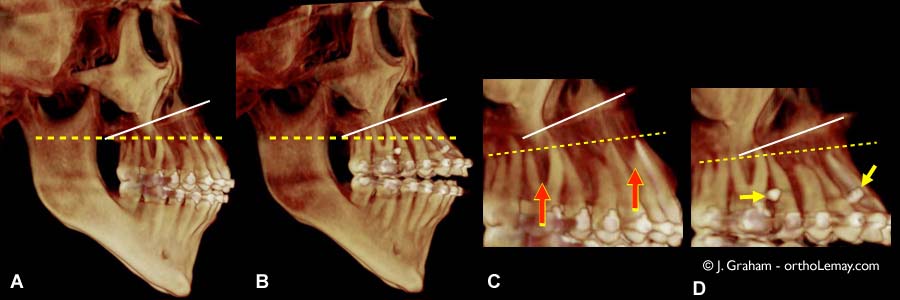

Changements verticaux dans la position des dents visibles sur un scan 3D ( tomodensitométrie volumique à faisceau conique (TVFC) ) avant et après le traitement d’ingression.